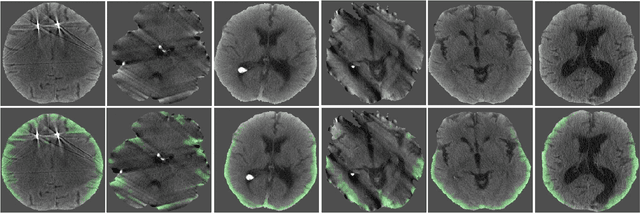

Computed tomography (CT) is the imaging modality used in the diagnosis of neurological emergencies, including acute stroke and traumatic brain injury. Advances in deep learning have led to models that can detect and segment hemorrhage on head CT. PatchFCN, one such supervised fully convolutional network (FCN), recently demonstrated expert-level detection of intracranial hemorrhage on in-sample data. However, its potential for similar accuracy outside the training domain is hindered by its need for pixel-labeled data from outside institutions. Also recently, a semi-supervised technique, Noisy Student (NS) learning, demonstrated state-of-the-art performance on ImageNet by moving from a fully-supervised to a semi-supervised learning paradigm. We combine the PatchFCN and Noisy Student approaches, extending semi-supervised learning to an intracranial hemorrhage segmentation task. Surprisingly, the NS model performance surpasses that of a fully-supervised oracle model trained with image-level labels on the same data. It also performs comparably to another recently reported supervised model trained on a labeled dataset 600x larger than that used to train the NS model. To our knowledge, we are the first to demonstrate the effectiveness of semi-supervised learning on a head CT detection and segmentation task.